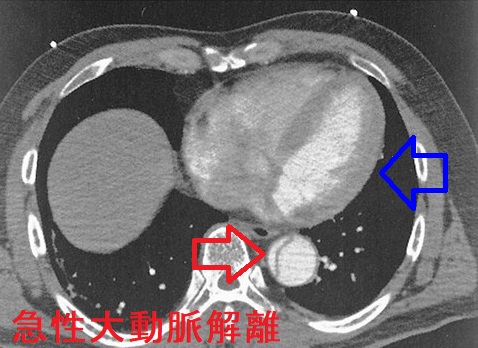

教科書に書いている「急性大動脈解離では心電図異常が無い」は大間違いです。A型の上行大動脈解離が大動脈基部に及ぶと、

- 心臓を栄養する冠状動脈入口部を圧迫し、急性心筋梗塞と同じ心電図所見になります。

- 大動脈弁閉鎖不全症(AR)を発症し、高調の拡張期雑音が胸骨右縁で聴取されます。心電図では左室高電位に。

- 心タンポナーデ(死因の一位);頸静脈怒張、I音とII音の減弱を認めれば、胸部CTより先に心エコー検査(最優先)